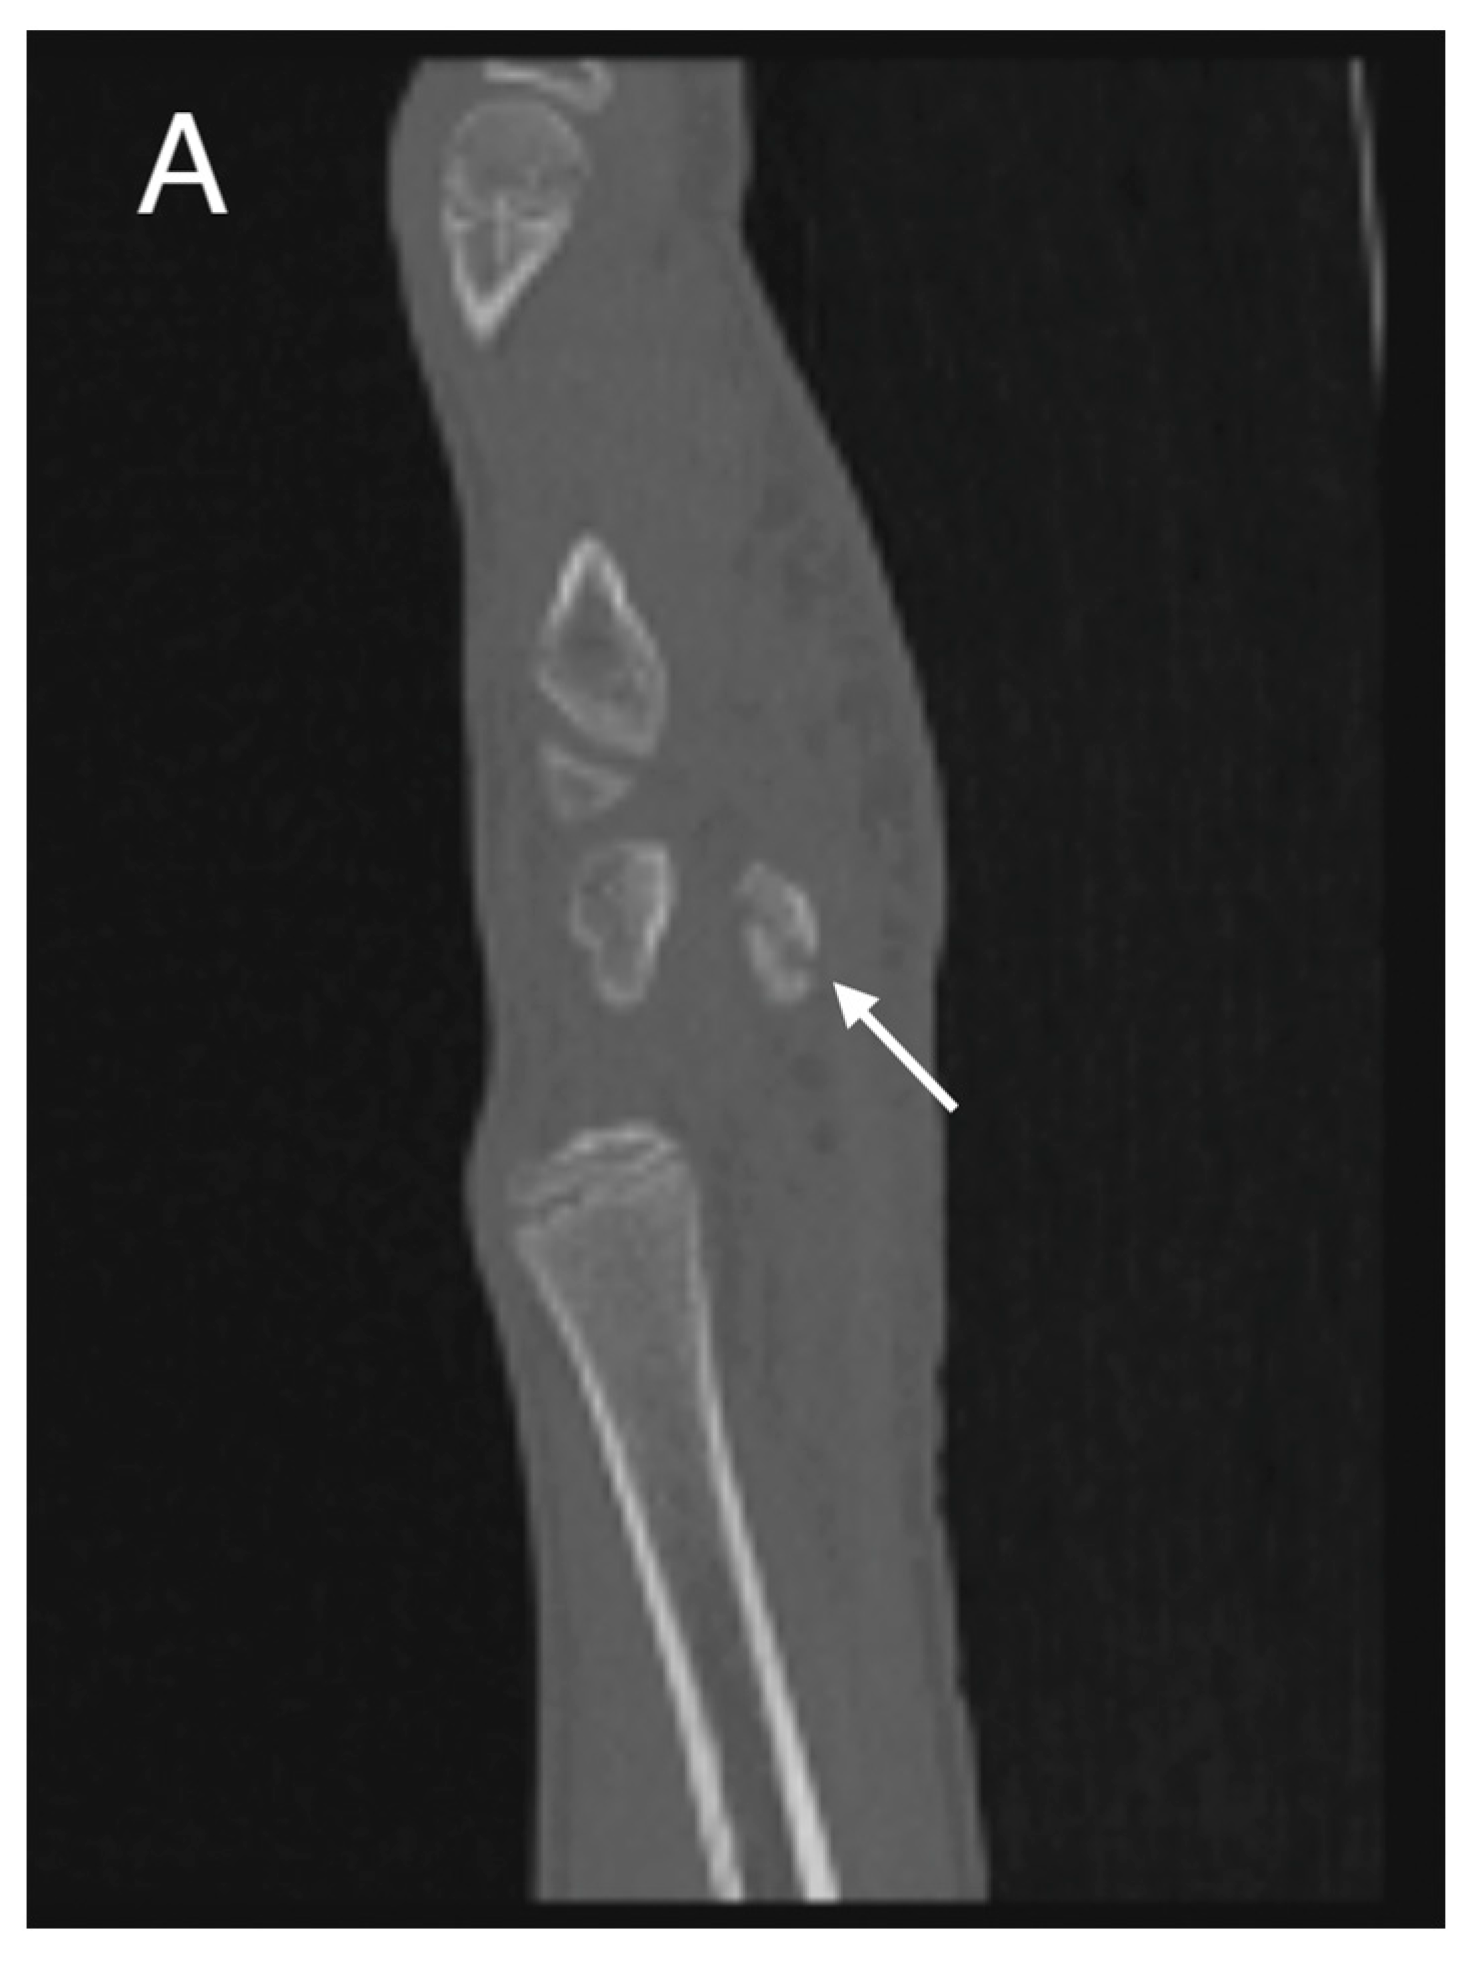

Initial conventional radiographic assessment showed no definitive fracture, with a potential suspicion of a proximal radius fracture (Figure 1). Due to significant tenderness over the radial fossa and pisiform, a CT scan was performed, confirming a nondisplaced scaphoid fracture and a suspected pisiform fracture with dislocation (Figure 2).

Figure 2.

Initial CT study with sagittal (A) and axial (B) images showing a non-displaced fracture of the pisiform bone (white arrows).